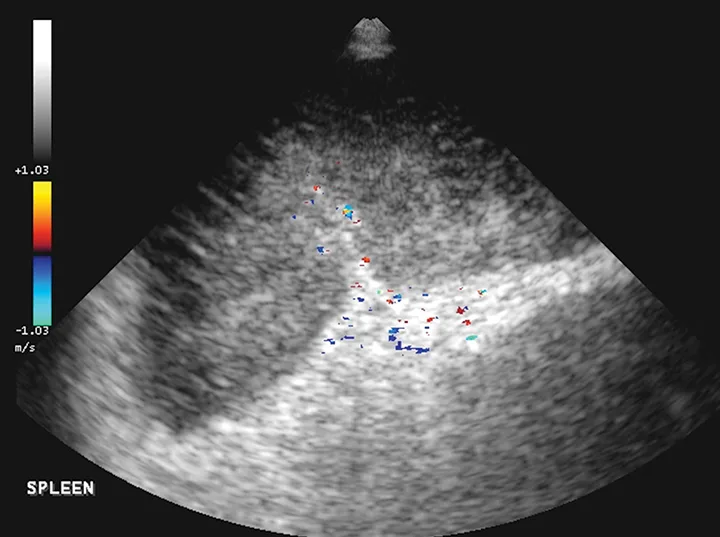

Treatment of the underlying disease in these conditions may relieve or reduce splenomegaly. In cases of splenic torsion (Figures 5 and 6), splenectomy is the recommended treatment, with approximately 90% of dogs surviving to discharge.19

FIGURE 5

Splenic torsion appears as a large soft-tissue opacity that displaces the GI tract caudally and peripherally (A). The splenic head is obscured caudal to the left margin of the stomach (B). The metallic opacity seen in the stomach and intestines is caused by recent barium administration.